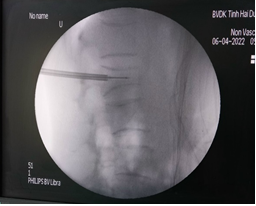

Bước 1: Xác định điểm vào thân đốt sống tổn thương thông qua cuống trên C-arm

Bước 2: Tiến hành sát trùng và gây tê tại vùng chọc kim gần với tổn thương nhất.

Bước 3: Tiến hành bơm thuốc cản quang để đánh giá, kiểm tra thành đốt sống có toàn vẹn hay không.

Bước 5: Đây là bước quan trọng nhất khi thực hiện kỹ thuật, xi măng sinh học sẽ được bơm qua kim định vị rỗng rỗng vào thân đốt sống bị xẹp. Tốc độ bơm phải chậm và được theo dõi chặt chẽ của bác sĩ thông qua C-arm và những biểu hiện lâm sàng của bệnh nhân như tình trạng đau hay cử động hai chân.

Bước 6: Để chắc chắn xi măng sinh học chỉ khu trú trong thân đốt sống, bác sĩ sẽ kiểm tra bằng C-arm hai bình diện thêm một lần nữa.